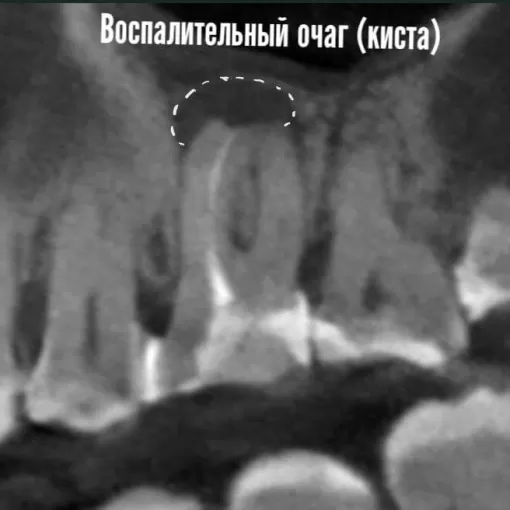

Вокруг корня з 4.7 наблюдается воспалительный очаг

Так в нашем клиническом случае вокруг корня з 4.7 наблюдается воспалительный очаг. Причина : инфекция в каналах. Ситуация осложняется сломанным инструментом (рис.1). Так под микроскопом с максимальным сохранением стенок корня был извлечен фрагмент инструмента (рис.2), удалена инфекция, проведена 3D пломбировка каналов. Уже через 6 месяцев мы наблюдаем заживление воспалительного очага и образование новой костной ткани (рис. 3)